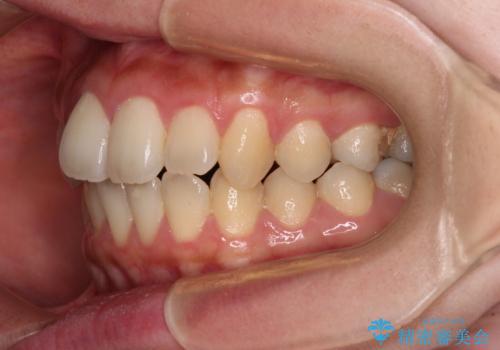

- 捻れた前歯が飛び出しており、口が閉じにくいとのことで来院された患者様です。

出っ歯というわけではないものの、前歯の捻転により口唇が押し出されている状態でした。

親知らずを抜去し、歯列全体を後方に移動させつつ、IPR(歯と歯の間を削る)でスペースを獲得し、インビザラインを用いて叢生を解消しながら前歯の突出を改善することとしました。

インビザラインは、患者様の協力無しには成立しない治療ですが、しっかりと装着時間を遵守してくださり、1年弱で治療を終えることができました。